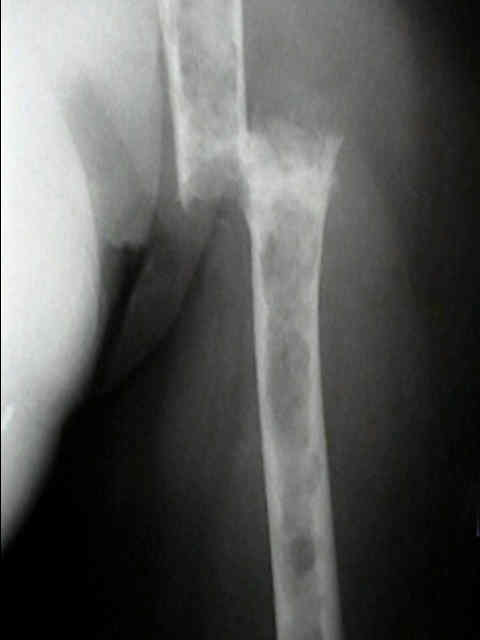

Radiographic Studies

- standard x-rays may show diffuse osteopenia

- "punched-out lesions" w/ no surrounding new-bone formation;

- over time lesions may change from diffuse osteopenia to more permeative moth-eaten destructive pattern, sometimes w/ cortical expansion;

- bone destruction occurs w/ little or no reactive bone formation unless pathologic frx is present;

Surgical Fixation

- Treatment of pathologic fracture of the humerus.